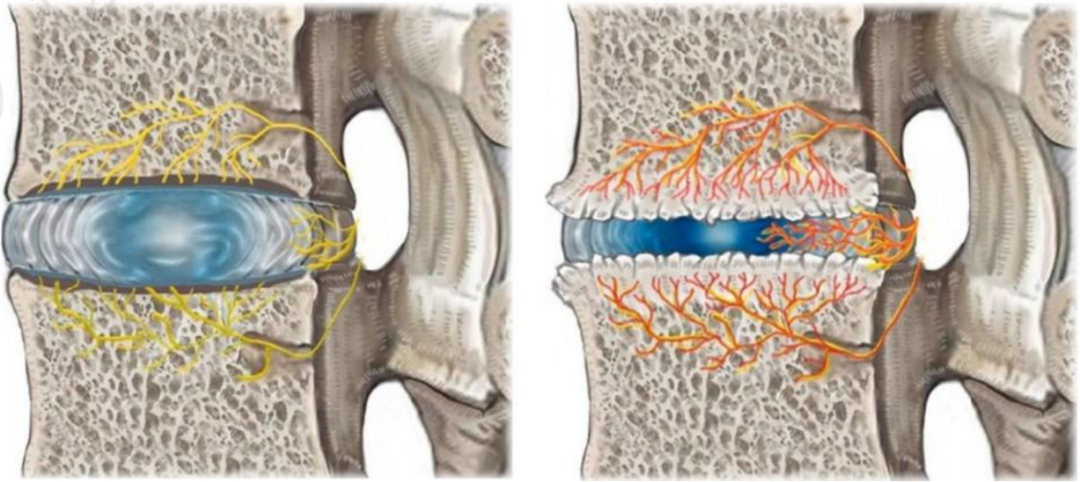

其实,椎体及终板的神经支配主要来自于窦椎神经的分支椎基神经,而椎基神经中 P 物质和 PGP 9.5 呈阳性反应,提示椎基神经可传递疼痛。生理情况下,终板的神经密度类似于外层纤维环。

然而,病变终板的神经密度明显高于无病变终板和病变的纤维环。

左图为正常的纤维环和终板神经支配情况,右图为病变的纤维环和终板,可见神经末梢向深层长入。

理论上讲,任何接受神经支配的腰椎及其相邻的软组织结构都可能是腰痛的起源部位。因此,Modic 改变有引起腰痛的解剖学基础。